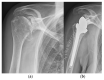

Osteoarthritis is a degenerative condition affecting the whole joint with the underlying bone, representing a major source of pain, disability, and socioeconomic cost worldwide. Age is considered the strongest risk factor, albeit abnormal biomechanics, morphology, congenital abnormality, deformity, malalignment, limb-length discrepancy, lifestyle, and injury may further increase the risk of the development and progression of osteoarthritis as well. Pain and loss of function are the main clinical features that lead to treatment. Although early manifestations of osteoarthritis are amenable to lifestyle modification, adequate pain management, and physical therapy, disease advancement frequently requires surgical treatment. The symptomatic progression of osteoarthritis with radiographical confirmation can be addressed either with arthroscopic interventions, (joint) preservation techniques, or bone fusion procedures, whereas (joint) replacement is preferentially reserved for severe and end-stage disease. The surgical treatment aims at alleviating pain and disability while restoring native biomechanics. Miscellaneous surgical techniques for addressing osteoarthritis exist. Advanced computer-integrated surgical concepts allow for patient personalization and optimization of surgical treatment. The scope of this article is to present an overview of the fundamentals of conventional surgical treatment options for osteoarthritis of the human skeleton, with emphasis on arthroscopy, preservation, arthrodesis, and replacement. Contemporary computer-assisted orthopaedic surgery concepts are further elucidated.